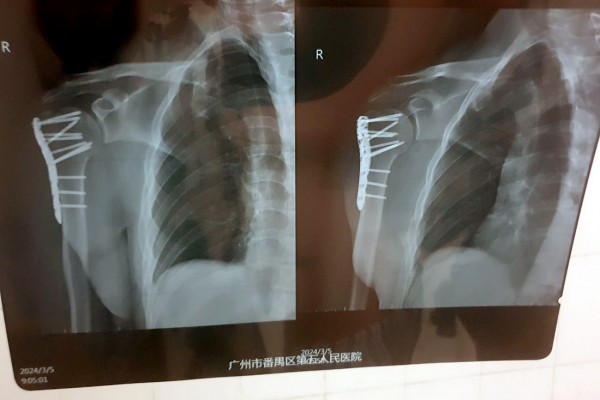

— Рука начала стремительно синеть, мне сразу сделали рентген и МРТ. Достаточно быстро стало понятно, что у меня перелом плеча со смещением. Боль была очень сильная, я не мог нормально пошевелить рукой. Врач сказал, что, возможно, потребуется операция. Мне пытались вправить плечо, но безуспешно. В итоге направили в хирургический отдел стационара, — говорит собеседник.

— Все это заняло около двух часов. Процесс не был приятным, так как я был в сознании и ощущал все манипуляции, проводимые на костях моего плеча, включая сверление, например. Была установлена пластина, которая зафиксировала поврежденные кости в правильном положении. После операции побочных эффектов не было, однако в течение еще шести часов врачи подключали различные датчики для контроля состояния. Все это время нельзя было есть и пить. А рука ощущалась как кусок бревна, — вспоминает читатель.

— Китайские врачи проделали по-настоящему хорошую работу. Это подтвердил знакомый белорусский хирург, взглянув на мои послеоперационные снимки. Думаю, не последнюю роль в этом сыграло и то, что я иностранец: мне показалось, что врачи особенно старались сделать все по высшему разряду. Также это хороший пример того, что надо смотреть не на вывеску больницы. Главное — это именно врачи и их отношение к своей работе, — считает молодой человек.

Белоруса выписали из больницы спустя три дня после операции. Впереди длительная реабилитация и еще одна операция — для того, чтобы изъять из плеча металлическую пластину.